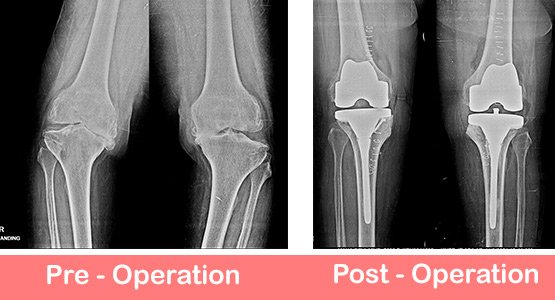

DITO is one of the top knee joint replacement hospitals in Delhi, India which provides a world class knee replacement surgical care facilities.

Report StoryDITO is one of the top knee joint replacement hospitals in Delhi, India which provides a world class knee replacement surgical care facilities.